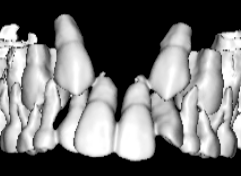

治療法:上顎急速拡大装置+クリアスナップ+フェイスマスク+上顎3番は開窓牽引CT写真にて位置確認

FX(フェイシャルアキシス)は85度なので東洋人の平均値に近く、下顎が前方に過剰成長するリスクは強くはありません。

しかしやはり上顎は劣成長で、下顎が優位な状態ではあります。

上下顎のギャップはありますが、顔面自体の幅径は良好な値を示していますので、スペース不足は拡大することによって解決できポテンシャルはあると考えられます。